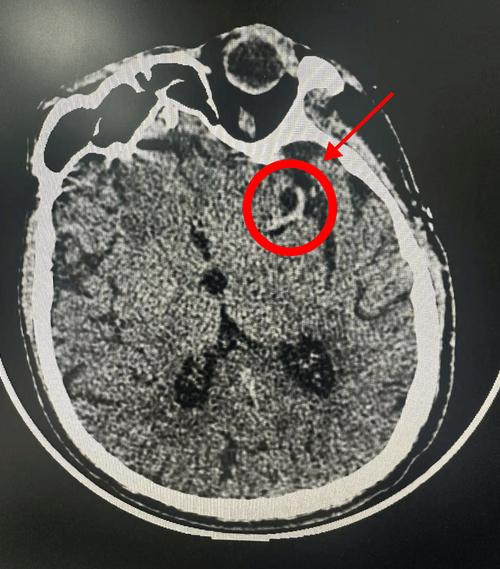

- 脑出血在CT上会显示为高密度(白色)的影像,非常清晰。

发病24-48小时后,梗死区域的脑细胞会因为缺血而发生坏死,此时CT上会显示出清晰的低密度(黑色)病灶,这可以帮助医生:

CT还可以帮助排除脑肿瘤、硬膜下血肿、脑脓肿等其他可能导致类似症状的疾病。